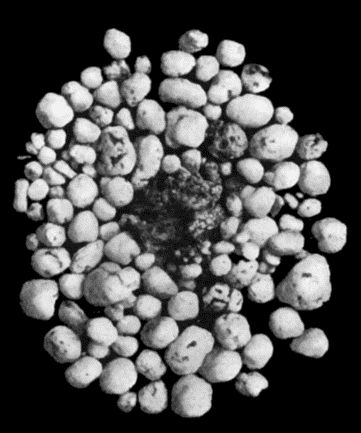

167.Loose Body from Knee-joint 541

77.Tuberculous Cervical Gland with Abscess formation 331